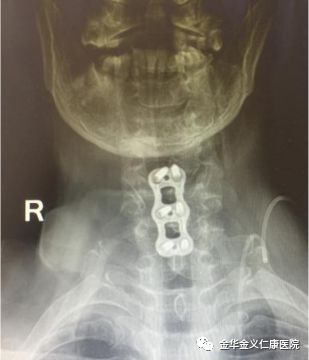

10月15日下午,经过两天的积极准备,由徐煜院长亲自操刀,为病人做了增生骨赘及突出椎间盘的切除手术。手术做得非常顺利。术后当晚,前几天痛得要死要活的她,疼痛完全消失,美美地睡了一觉。术后在全科医护人员的悉心照护下,身体状况恢复很快,术后第三天,就在家人及护理人员的协助下下地行走了。术后患者感慨地说,知道手术效果这么好,恢复这么快,我早就应该考虑手术了,起码可以少吃很多苦头!

术前术后对比